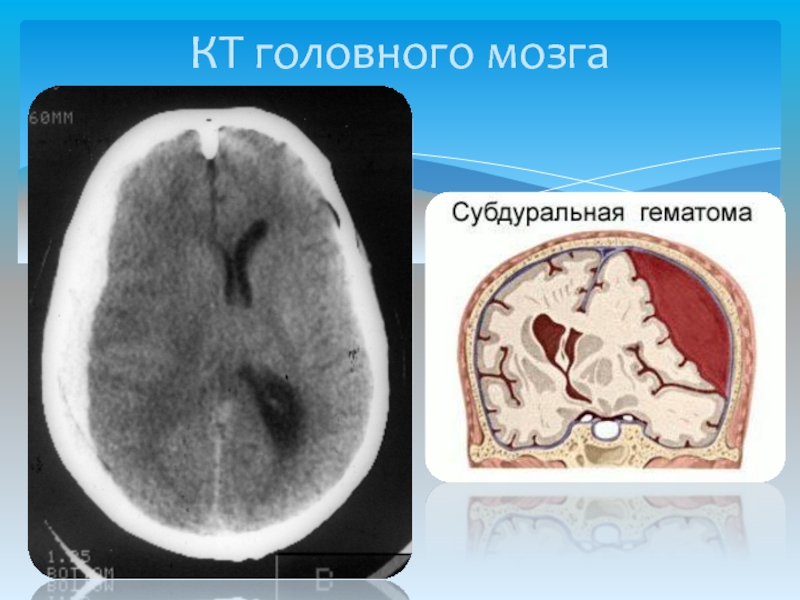

Медицинские аспекты и диагностика субдуральной гигромы мозга